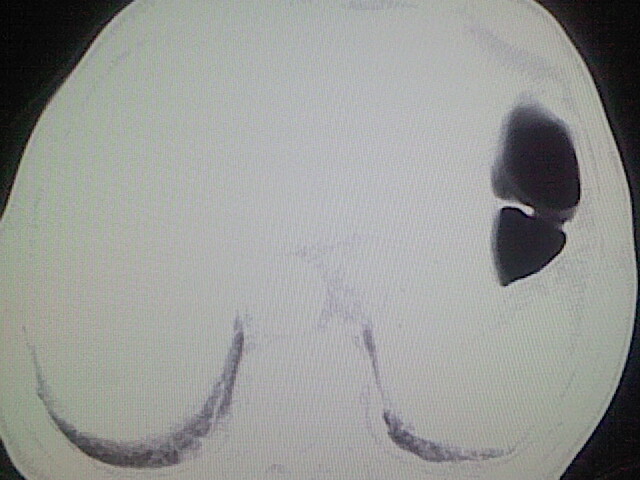

以下是引用zsl6918在2008-8-28 16:49:00的发言:[br]双肺炎性病灶,食管狭窄估计与心房增大压迫所致。

以下是引用xulianj在2008-8-28 20:36:00的发言:[br]慢支肺气肿伴感染,右上肺陈旧性结核;食道建议胃镜检查。

以下是引用wqs571018在2008-8-28 21:18:00的发言:[br]慢支继发感染,右上肺陈旧性结核;食道建议胃镜检查。